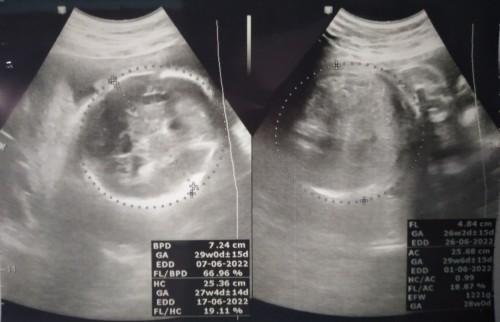

Assalamu'alaikum bumil semuanya Selamat menjalankan ibadah puasa. Alhamdulillah hamil 7 bulan.tepat hari ini 31 week dedek lincah banget diperut.kadang rasa nyeri kalo pas ketendang pinggang.kira2 bayinya tidur apa gak ya soalnya koq geraknya aktif banget bunda....? #ingintahu